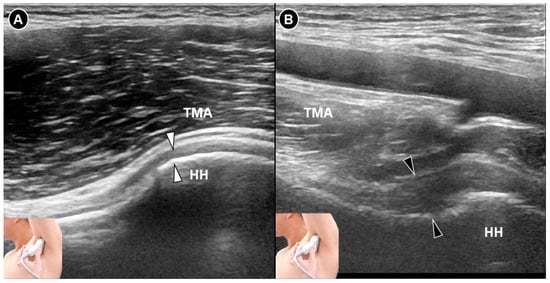

Figure 2. Ultrasound imaging of the inferior glenohumeral joint (white arrowheads) in a normal shoulder (A). In contrast, imaging of the inferior glenohumeral ligament (black arrowheads) in a shoulder with adhesive capsulitis reveals thickening of the inferior glenohumeral capsule (B). HH, humeral head; TMA, teres major.

In parallel, Michelin et al. [28] conducted a retrospective ultrasound study evaluating inferior capsule thickness in 20 patients with unilateral capsular contracture confirmed either clinically or by magnetic resonance imaging. Using the axillary approach during maximal abduction, they measured the inferior glenohumeral capsule orthogonally to the inferior glenohumeral ligament. The average capsule thickness was significantly greater in affected shoulders (4.0 mm) than in asymptomatic contralateral shoulders (1.3 mm), with a p-value < 0.0001. These results not only reinforce the diagnostic relevance of inferior capsule thickening but also emphasize the utility of standardized measurement techniques in improving the sonographic assessment of adhesive capsulitis. This study has several limitations. It only included patients with clinically evident stiff shoulders, limiting applicability to earlier disease stages, and did not assess the reliability or measurement error of the ultrasound technique. Additionally, the monocentric design and small sample size warrant confirmation through larger prospective studies.